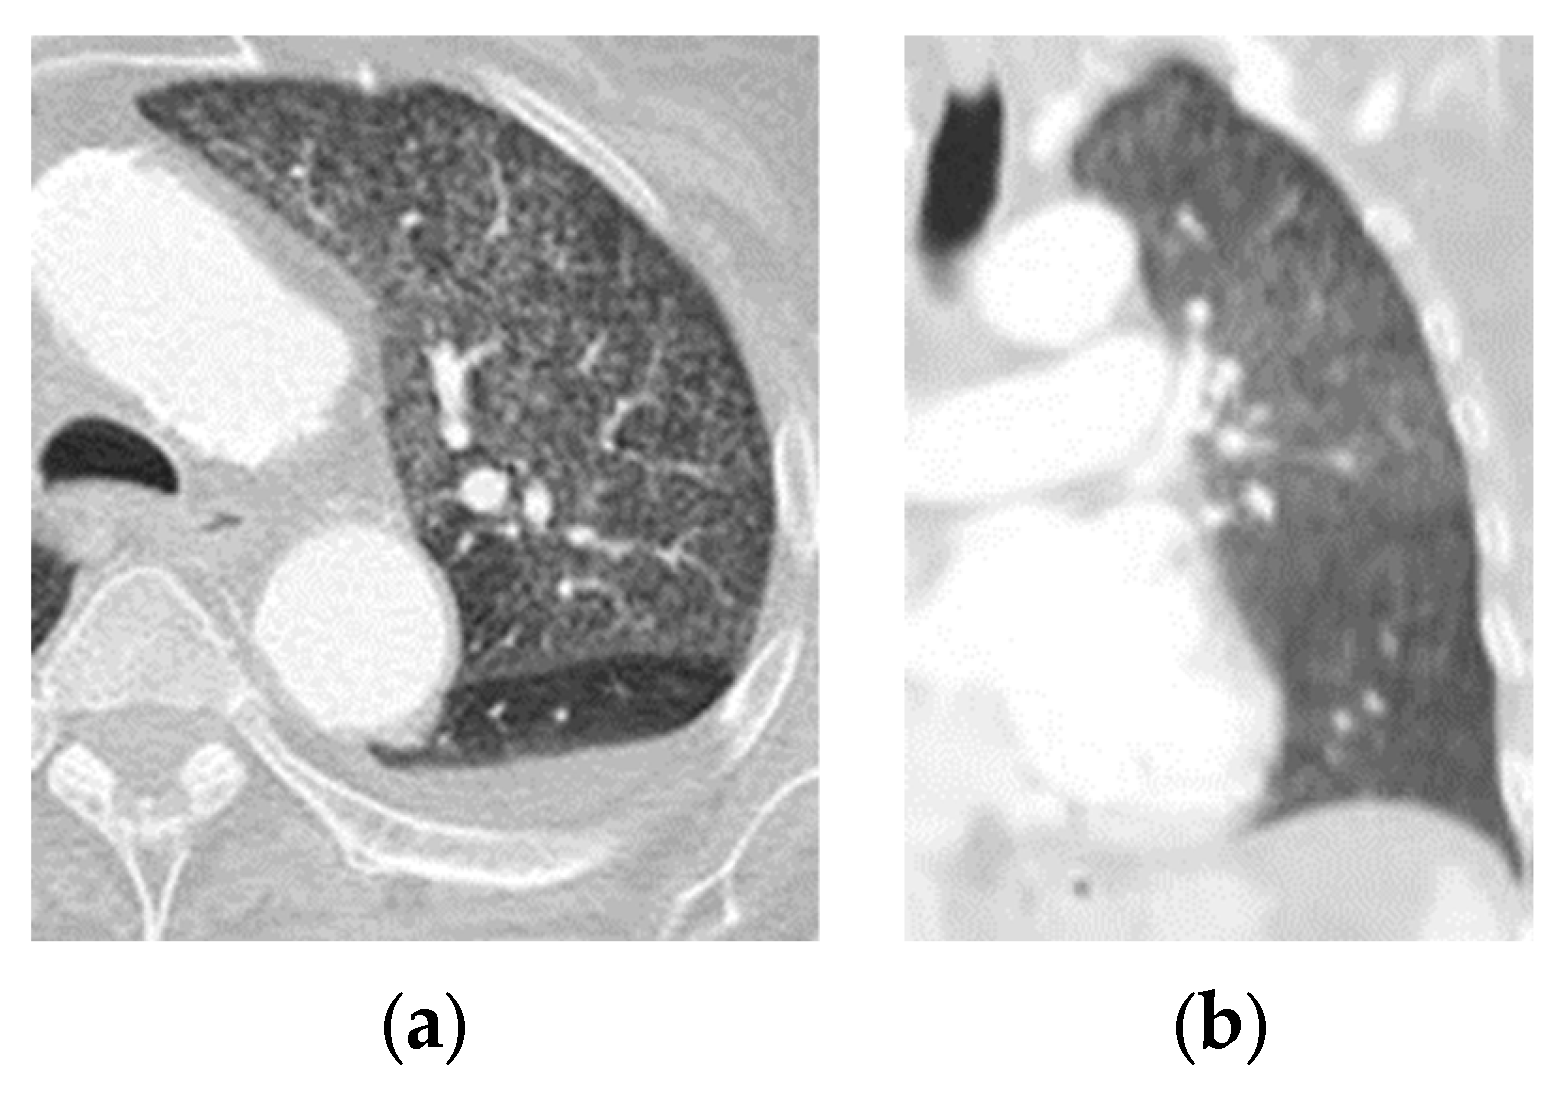

CO-RADS 1: negative; normal examination or findings not associated with a pulmonary infection (Figure 1).

(a) Axial section and (b) coronal section of a patient who underwent an RT–PCR test for SARS-CoV-2 upon admission. The finding was negative. He was discharged after improvement at 3 weeks following admission.